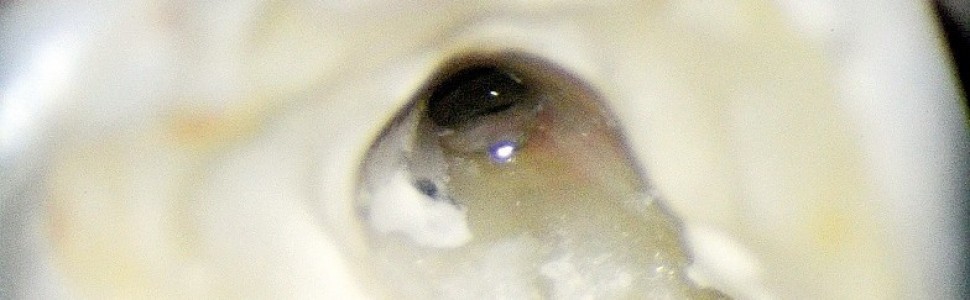

Widoczna perforacja zlokalizowana dopoliczkowo od gutaperki i uszczelniacza wypełniającego kanał podniebienny, w której obręb zostaje wprowadzony zgłębnik.

Osuszenie ujścia kanału podniebiennego za pomocą kulki z waty, a następnie kanału perforacyjnego za pomocą sączka papierowego; na szczycie sączka widoczna krew.